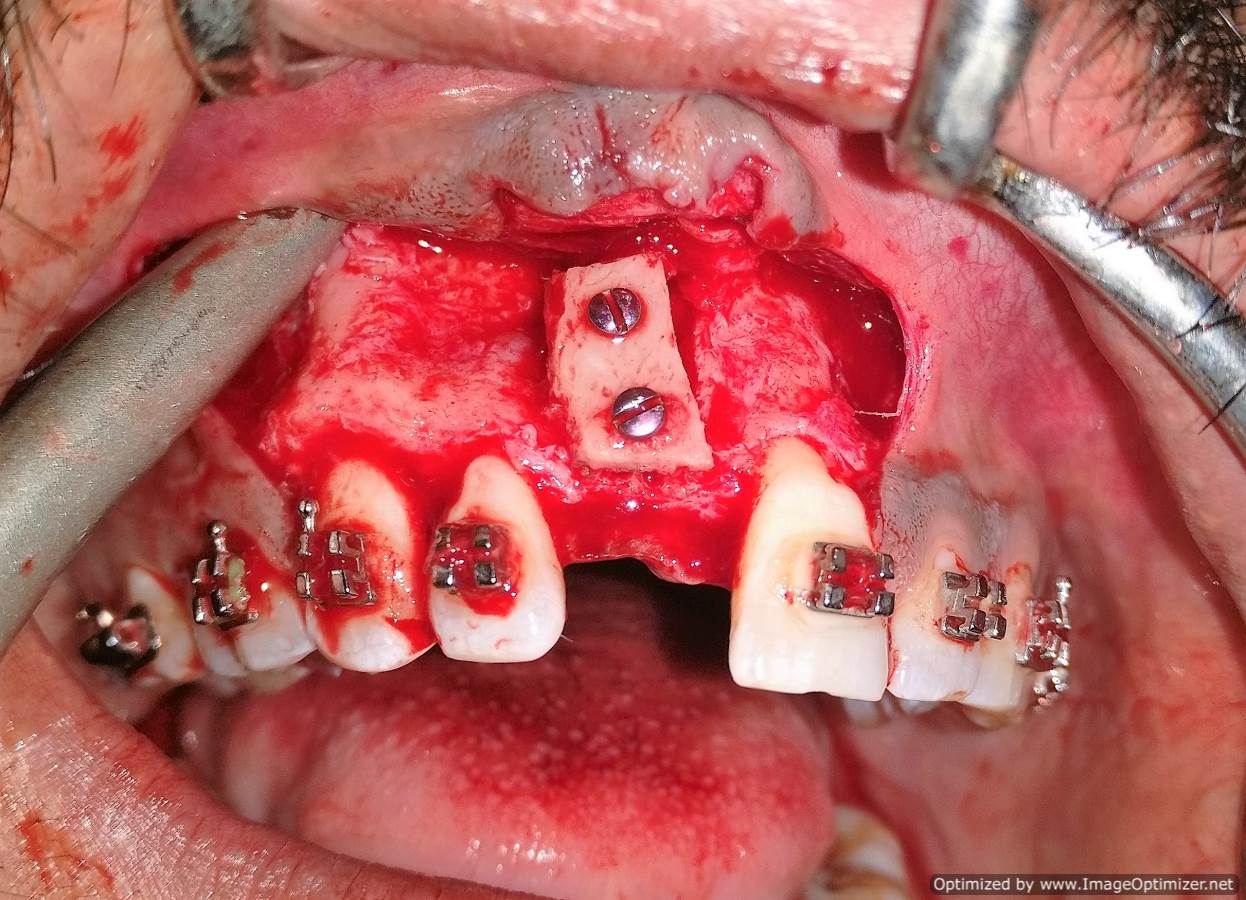

Dental Implant Case Report -03

Home / Case Report / Implant / Dental Implant Case Report -03